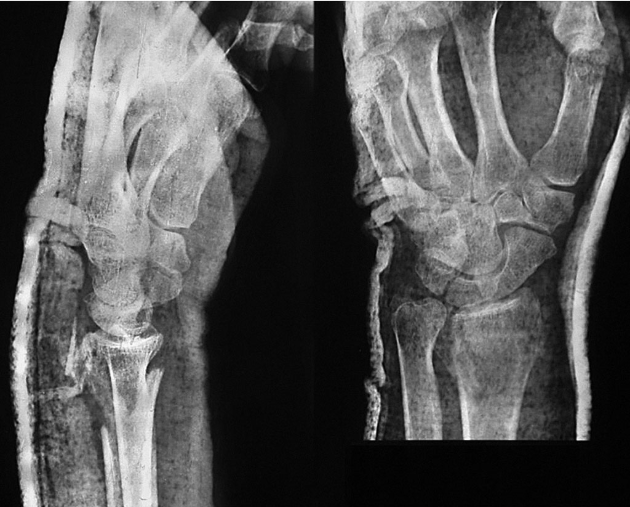

患者,女,51岁。因右腕摔伤后肿痛、畸形、活动受限,急诊就诊诊断为右桡骨远端骨折。行闭合牵引复位,石膏托外固定。拍片复查,桡骨远端背侧因骨折的粉碎性质而缺损巨大,背侧的皮质骨碎片向远端移位至桡腕关节间隙水平并嵌于腕背软组织中无法闭合复位(图2-1)。桡骨远端背侧因缺乏可靠的皮质骨支撑而存在骨折继发移位、掌倾角向背侧倾斜且移位的皮质骨碎片潜在刺激背侧软组织、磨损伸肌腱的风险,增加发生关节疼痛和功能障碍的可能性,于是行桡骨远端骨折切开复位,人工骨植入,超关节外固定架固定术。

图2-1 桡骨远端背侧因骨折的粉碎性质而缺损巨大,背侧的皮质骨碎片向远端移位至桡腕关节间隙水平并嵌于腕背软组织中无法闭合复位

桡骨远端不稳定骨折是主要的手术指征,包括:①桡骨远端背(掌)侧皮质粉碎,关节面移位>2mm;②掌倾角向背侧倾斜超过20°~25°;③桡骨短缩> 5mm;④复位后不稳定,易发生再移位。骨折在纵向牵引下骨折块复位困难,骨折端的骨皮质支撑不满意,在骨折端夹有肌腱或骨膜。对于严重的关节内粉碎骨折,桡骨短缩明显,内固定螺钉无有效固定位置的病例,外固定架固定是首选方法。如Frykman分型中的Ⅶ、Ⅷ两型,通用分类法中的Ⅱ、ⅣA、ⅣB型,关节内四部分骨折等首先应考虑外固定架。此患者桡骨远端背侧皮质粉碎,复位后不稳定,易发生再移位。腕背侧移位的骨片闭合复位很难达到满意的位置。